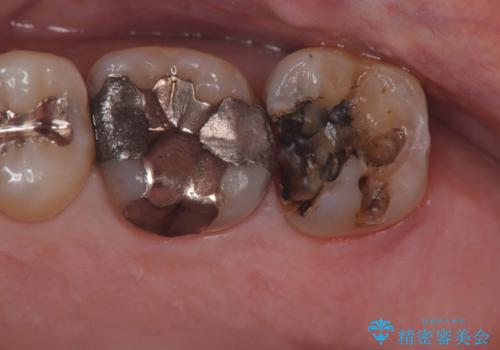

【フルジルコニアクラウン】銀歯二次カリエス!

今回も不適合な銀歯を外したらその下は虫歯になっていました。

不適合な銀歯を外して、虫歯の除去後にシリコンで印象をとりフルジルコニアクラウンで治療を行いました。